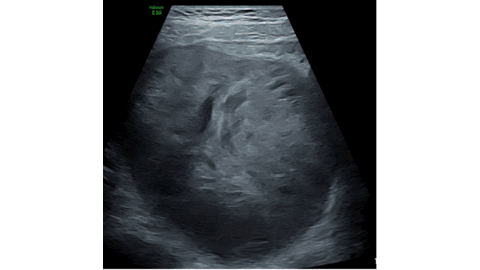

Case Presentation: A 9-year-old female child was brought with the complaints of acute right lower quadrant pain, nausea and vomiting. On examination, the abdomen was tender with guarding. Laboratory investigations revealed leukocytosis, raised inflammatory markers and markedly elevated alpha-fetoprotein (AFP) levels. Ultrasonography revealed a mixed echogenic tumor in the right adnexa with features of adnexal torsion. Cross sectional imaging confirmed the presence of a heterogeneously enhancing tumor in the right adnexa with pelvic and paraaortic lymphadenopathy. Subsequently, the child underwent emergency laparotomy for adnexal detorsion with tumor excision. Postoperative histopathological examination confirmed malignant yolk sac tumor.